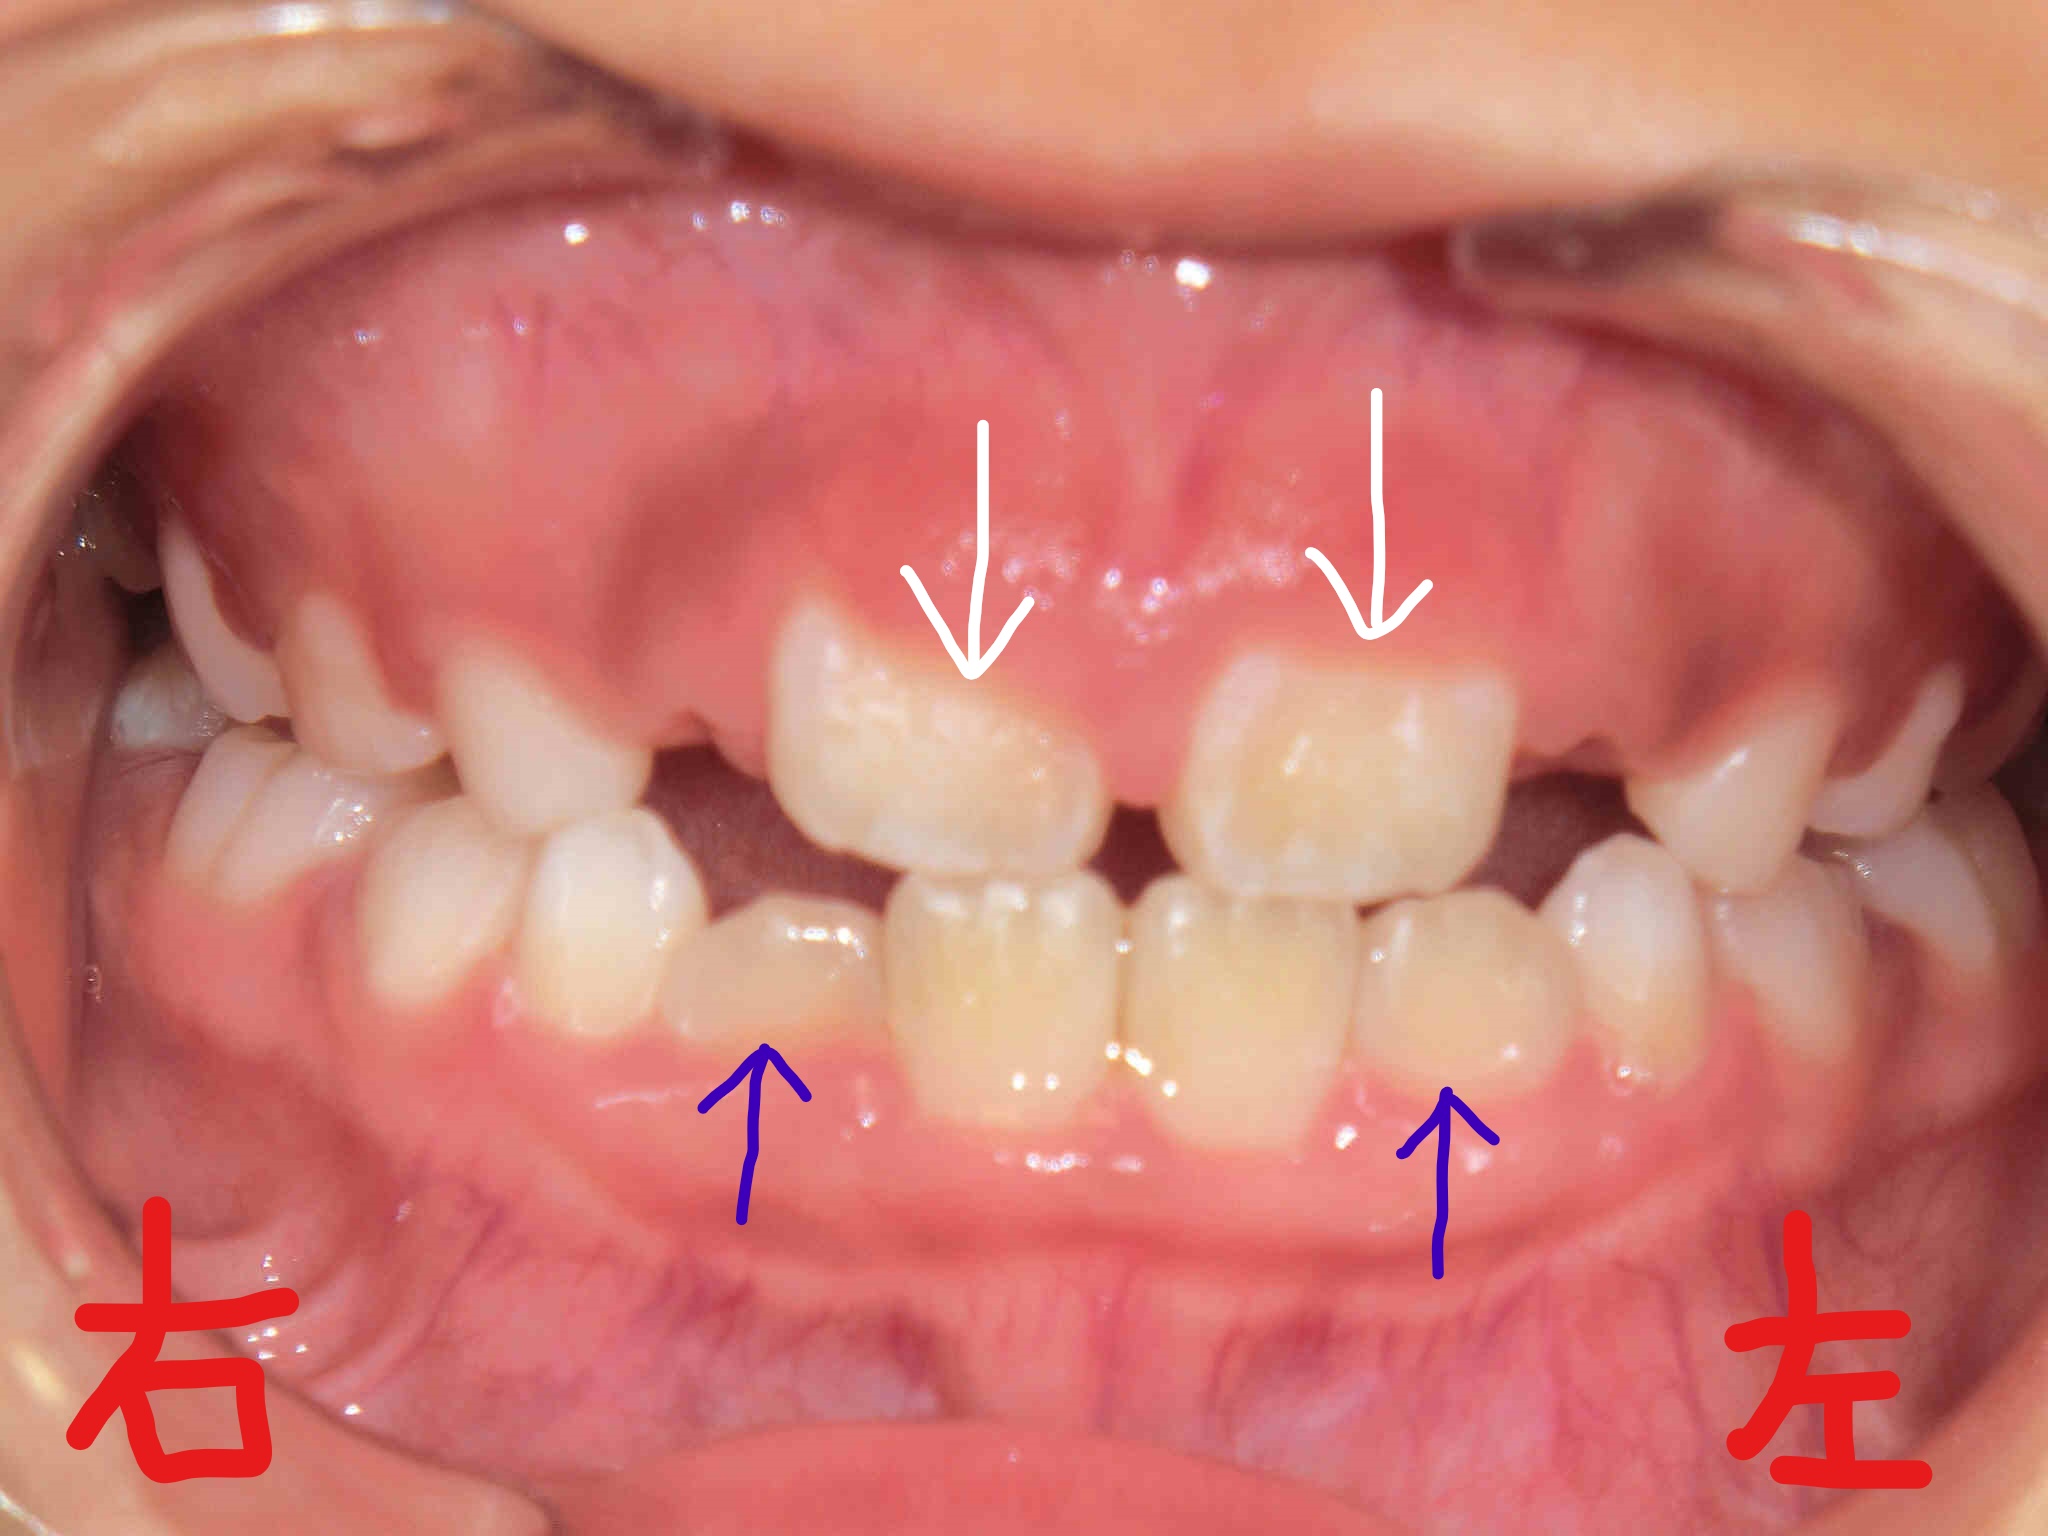

左上の写真は、2017年2月時点の正面から見た歯並びです。下顎前歯(青色矢印)がかなり内側に萌出しており、上顎前歯(白色矢印)も「八の字」に萌出しているのが確認できます。

右上の写真は2017年8月時点の同様の正面写真です。やはり下顎前歯(青色矢印)が前方に整列され、上顎前歯(白色矢印)の「八の字」状の萌出が改善されつつあるようすがうかがえます。

当院、みらい歯科・矯正歯科クリニック では、取り外し式の筋機能矯正装置(例:〈マイオブレイス〉、〈K1〉、〈プレオルソ〉)をお使いいただき、日中1〜2時間および就寝時に装着していただきました。同時に、あいうべ体操など代表的な口腔筋機能療法(MFT)を継続して実践していただいた結果、矯正開始後わずか6か月という短期で歯並びが劇的に改善されたのがご覧いただけると思います。

なお、治療期間は6か月(現在治療中)、来院回数は6回、治療費は調整料を含めて336,960円(税込)でした。